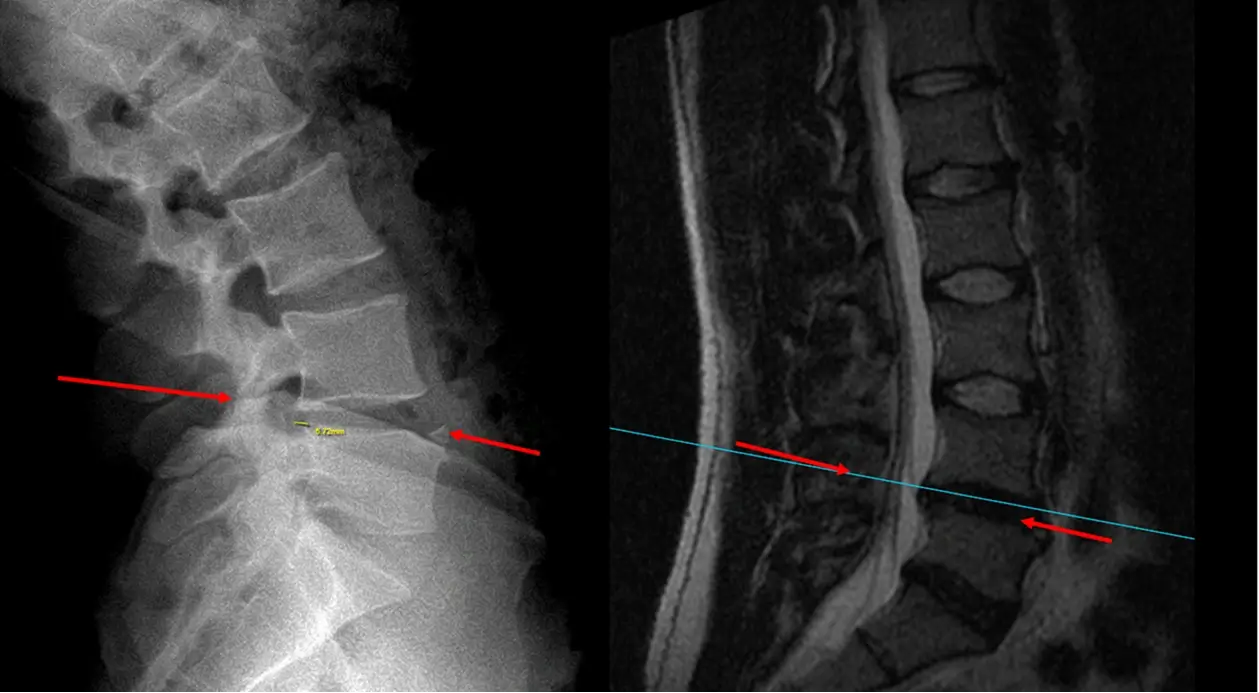

Pre OP MRI and radiograph sagittal view

Pre OP radiographs, frontal and sagittal views